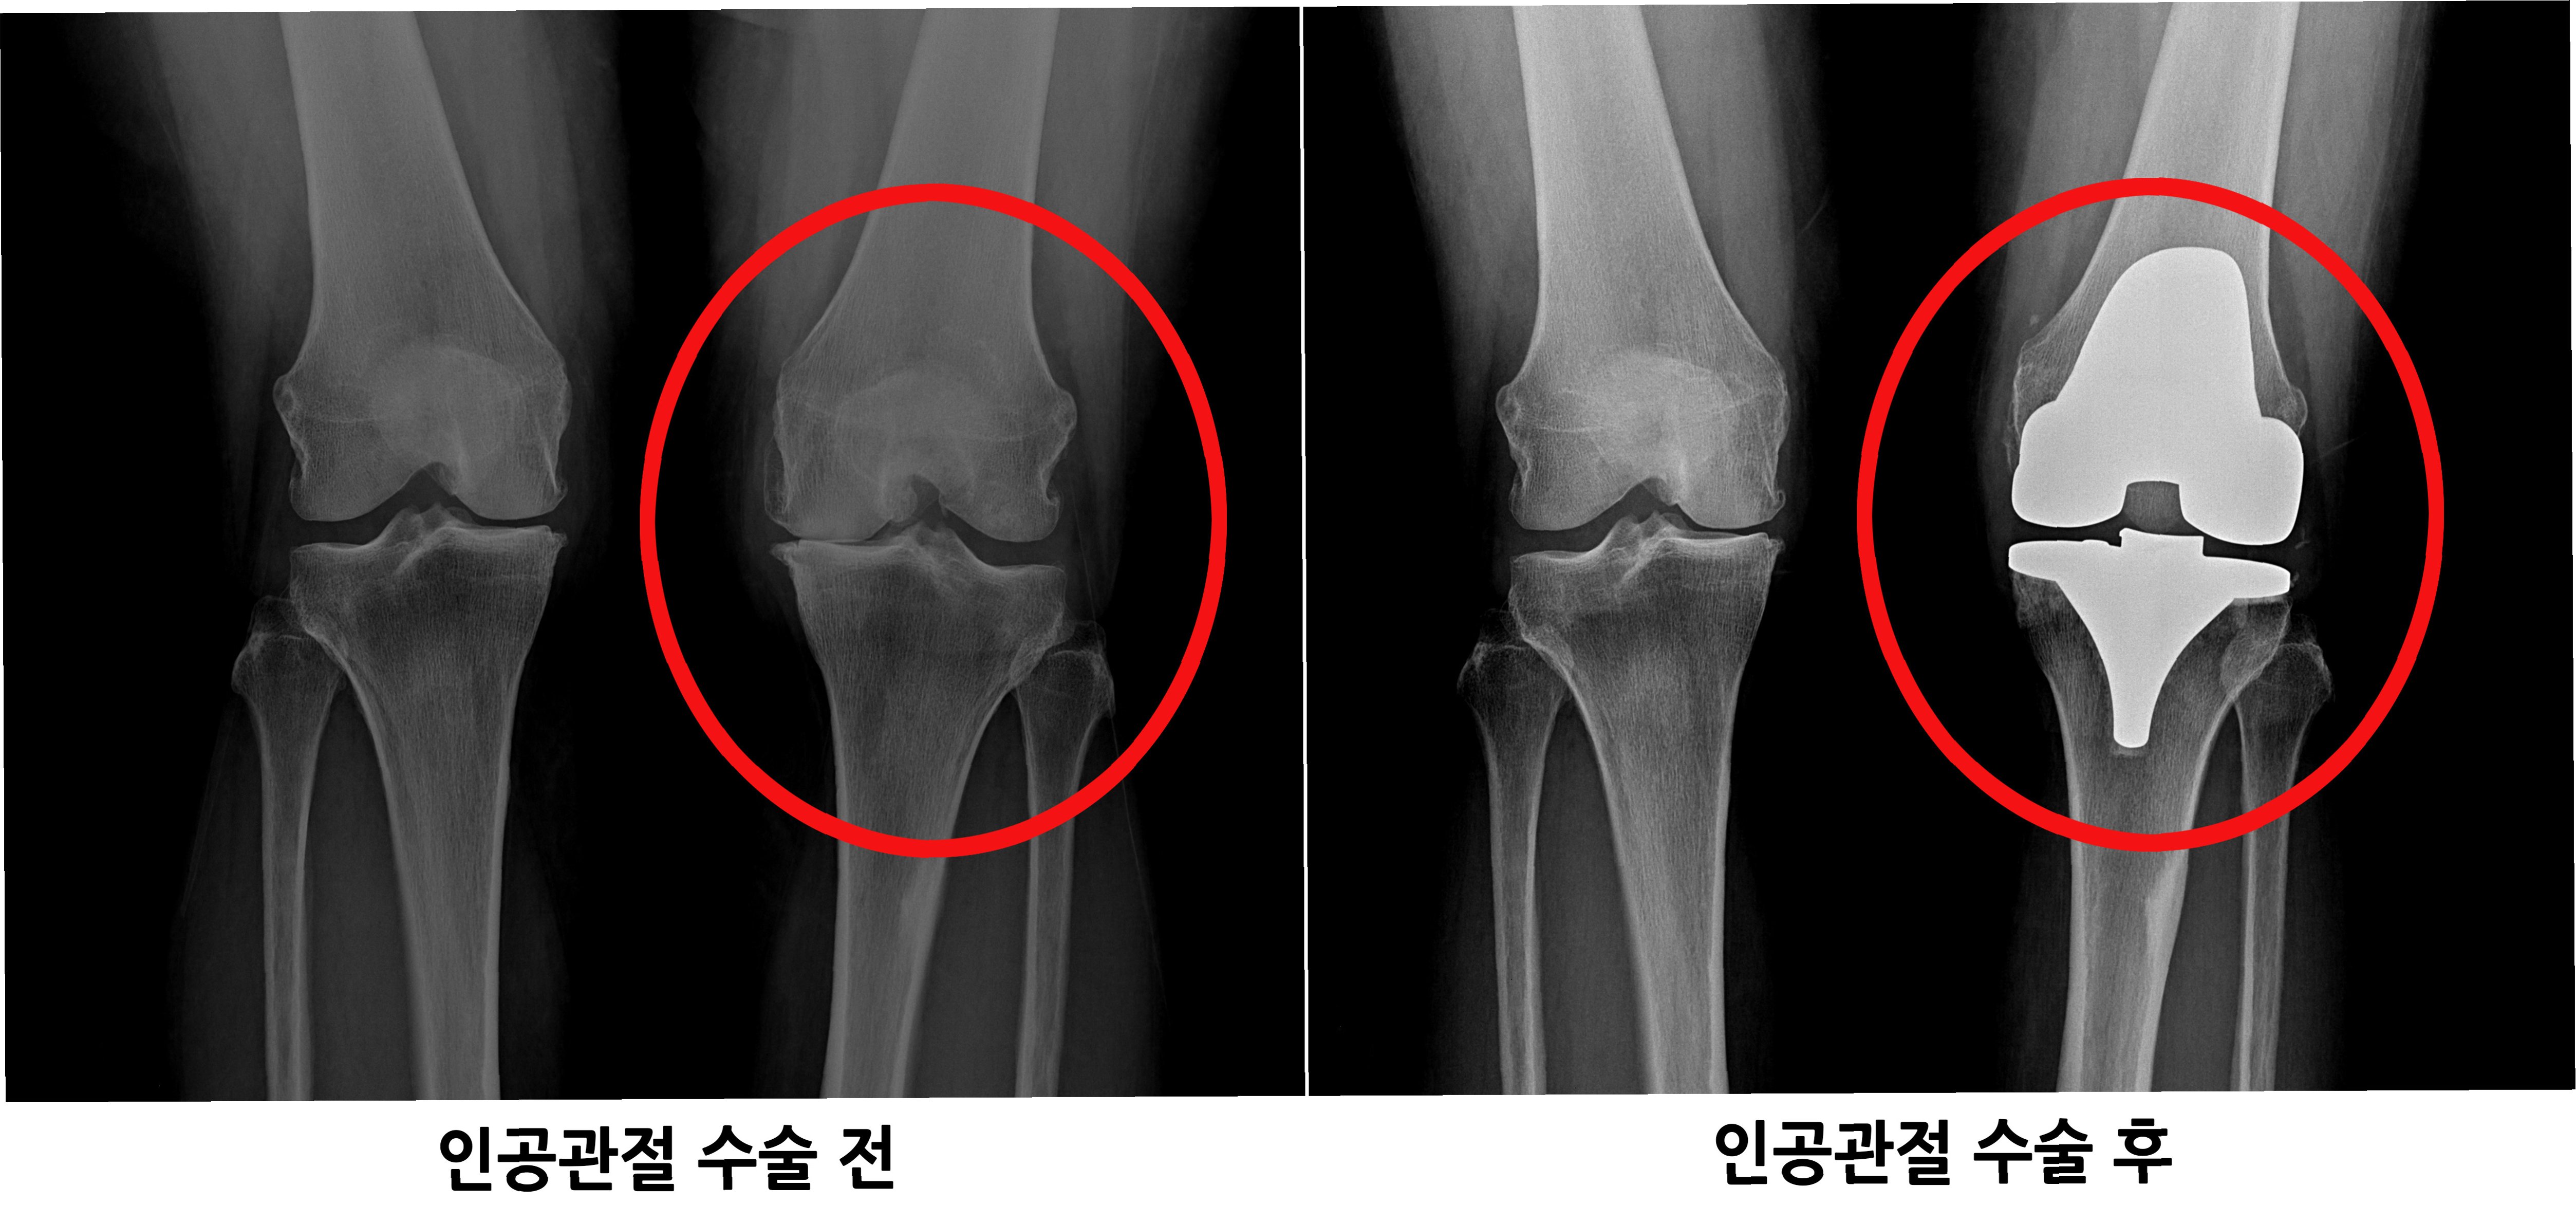

인공관절수술은 일반적으로 손상된 관절 부위를 절개하고, 손상된 뼈와 연골을 제거한 후 인공관절을 삽입하는 방식으로 진행됩니다. 수술 시간은 관절 부위, 수술 방법, 환자의 상태에 따라 다르지만, 대개 1~3시간 정도 소요됩니다. 수술 후에는 통증 관리와 함께 조기 재활 운동을 시작하여 관절의 기능 회복을 돕습니다. 초기에는 보행 보조기구(목발, 보행기 등)를 사용하며, 점차적으로 사용 빈도를 줄여나갑니다. 재활 운동은 관절의 가동 범위를 늘리고 근력을 강화하여 일상생활 복귀를 돕는 데 매우 중요합니다. 회복 기간은 개인의 상태, 수술 방법, 재활 노력에 따라 다르지만, 일반적으로 수술 후 3~6개월 이내에 일상생활로의 복귀를 목표로 합니다. 꾸준한 재활과 관리를 통해 건강한 관절 기능을 회복하고 오랫동안 유지할 수 있습니다.

1. 퇴행성 관절염: 관절 연골이 닳아 뼈와 뼈가 직접 닿아 통증과 염증을 유발하는 질환입니다.